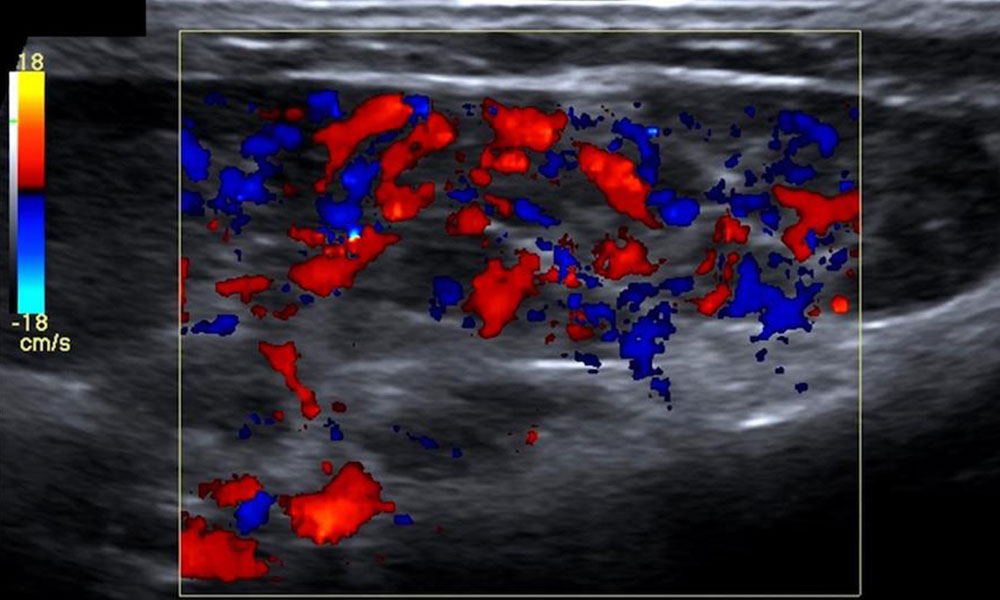

• Infantile hemangioma: The main feature during the proliferative phase is strong hypervascularization in color-coded duplex sonography. The parenchyma is relatively anechoic. In contrast to a true arteriovenous malformation, a solid mass is usually visible. This hypervascularization decreases significantly during the involutional phase. The echogenicity, on the other hand, increases because of fatty remodeling.